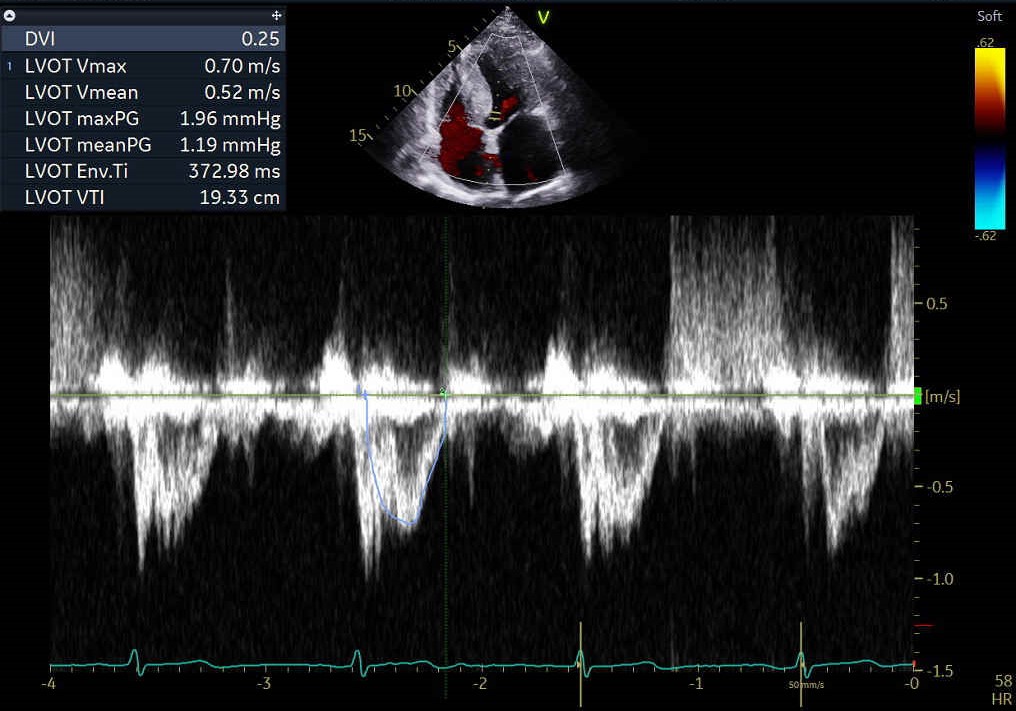

The echocardiographic findings indicate an LVEF of 55%, an aortic valve area of 0.77 cm², a maximum velocity of 3.28 m/s, a mean pressure gradient of 22 mmHg. Intermittent shortness of breath and heart failure symptoms have been reported for more than six months and are deemed to be related to low flow, low gradient severe aortic stenosis. His surgical risk, represented by an STS score of 12.4%, reinforces the decision to proceed with the TAVI intervention.